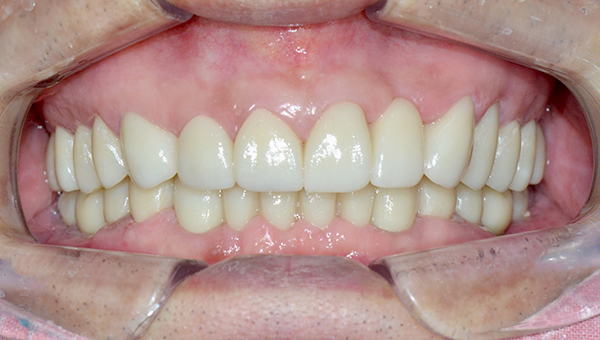

심*복 임플란트 시술 사례

전체 임플란트

2024.12.05

치료 전

2025.05.30

치료 후